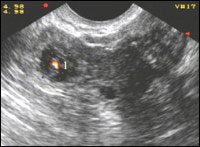

| Рисунок 7 |

|

Рисунок 8 |

| Эхокартина внематочной беременности |